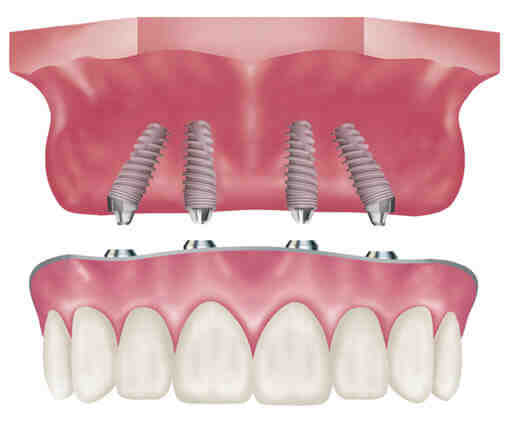

Is all on 4 implants good?

All-On-4® implants have a high success rate, and for many people they work well and last for decades, which they should. See the article : Permanent False Teeth. Statistically, all on 4 implants have a higher success rate of 97 percent.